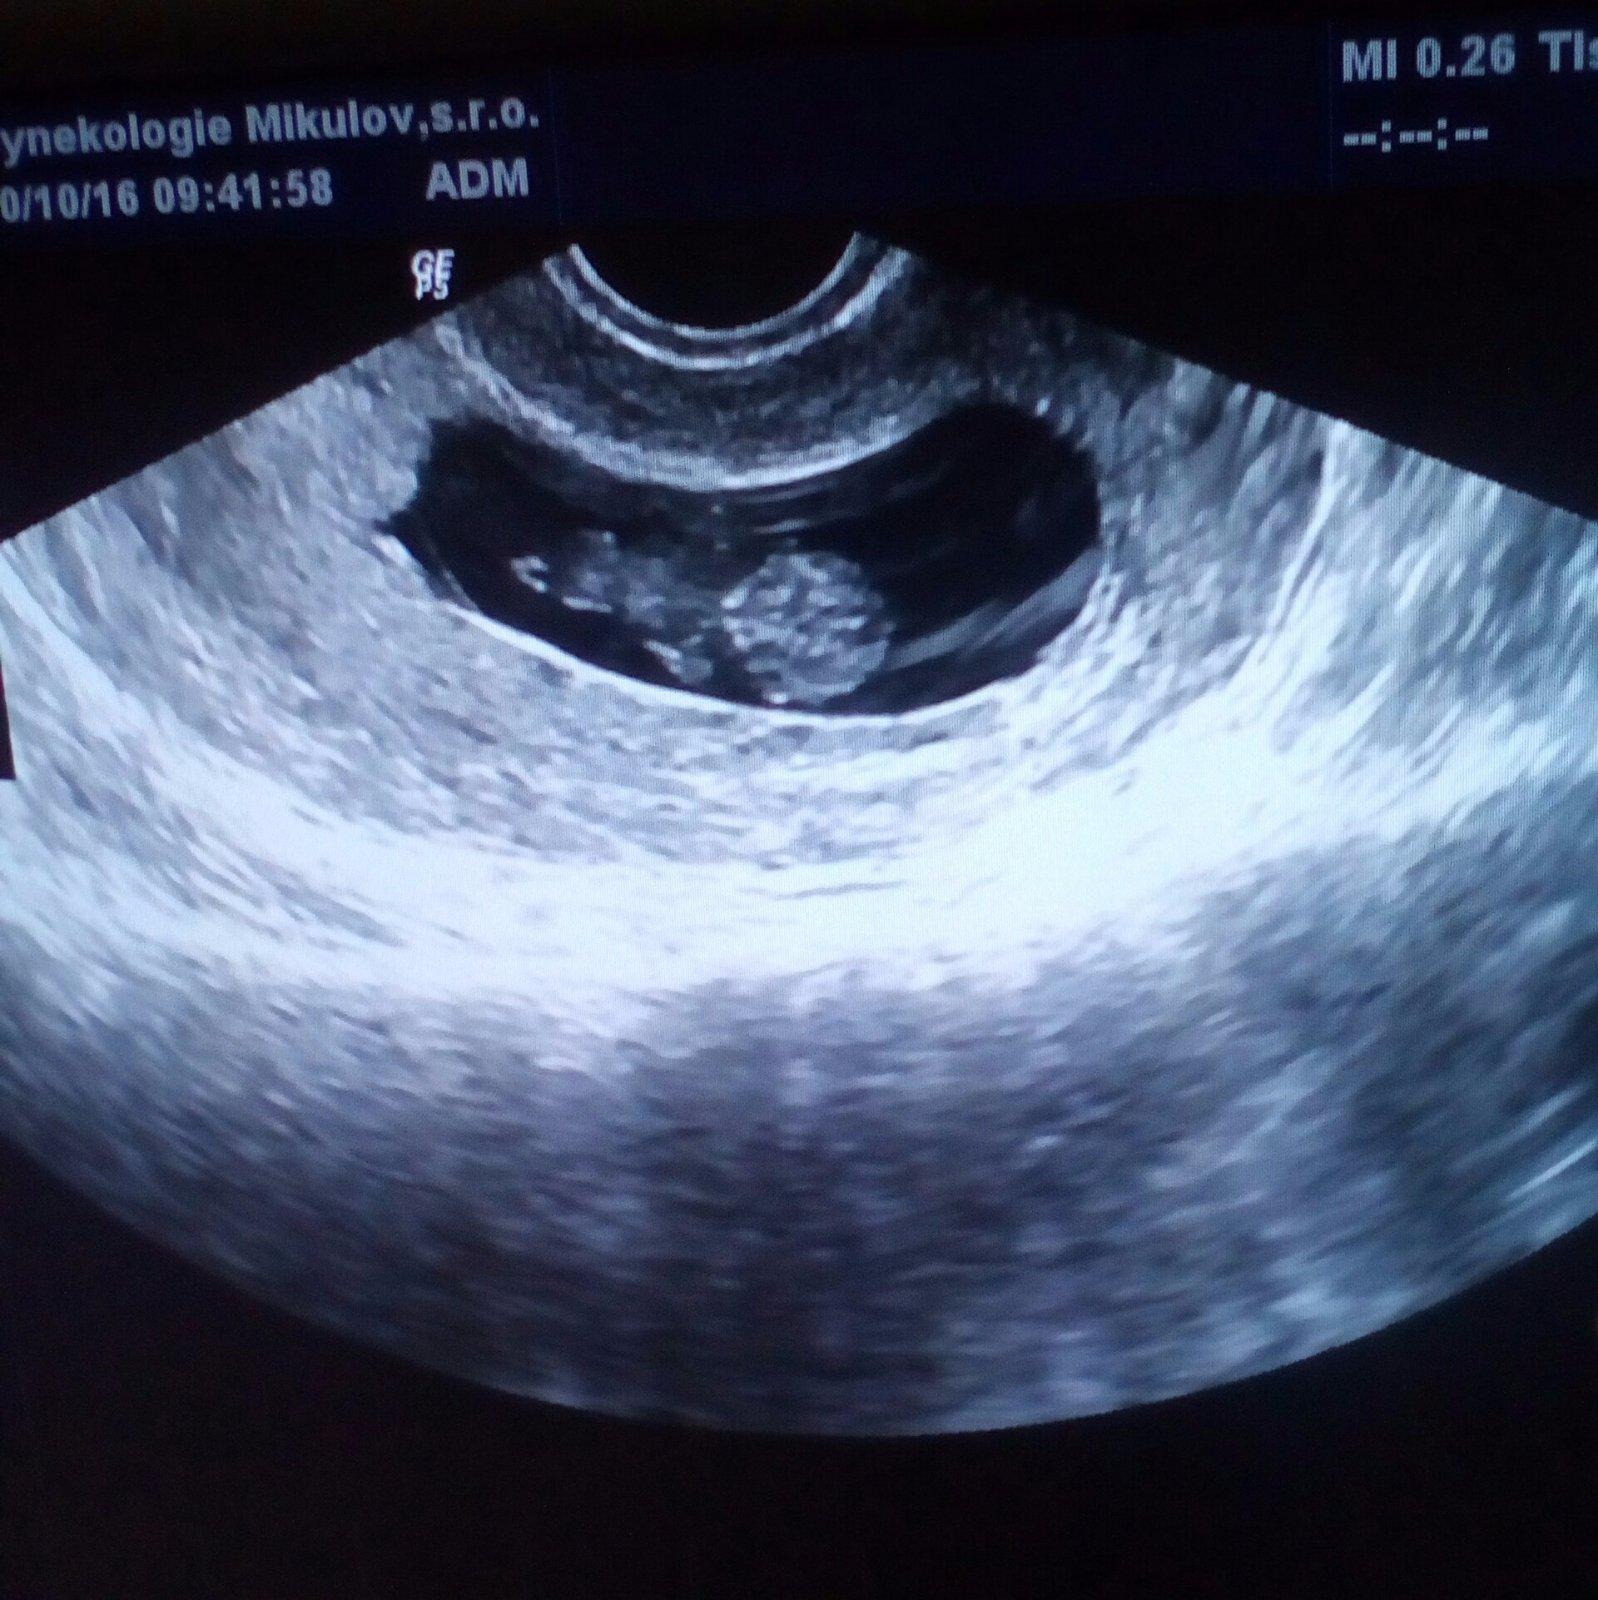

@lucienelka já jsem 5+3 a byl vidět jen gestační váček, ale při prvním synovi bylo v 5 týdnu vidět už i primitivní srdíčko, takže ono jde asi o to, kdy přesně bylo vajíčko oplodněno. U nás asi až dýl, než při prvním těhu. a dr mě objednal za 10 dní, takže podle mě nemusíte čekat tak dlouho. Prý už za těch 10dní bude vidět víc.

@europa00 říkala nějak 178. Na ultrazvuku byla vidět jen malá dutinka, doktorka říkala, že jestli je to v pořádku, tak to odpovídá opravdu tak 2.týdnu od početí, takže tam nebylo vidět skoro nic. Že víc bude sand příští týden, pokud to poroste. Příští úterý jdu na kontrolní UTZ.